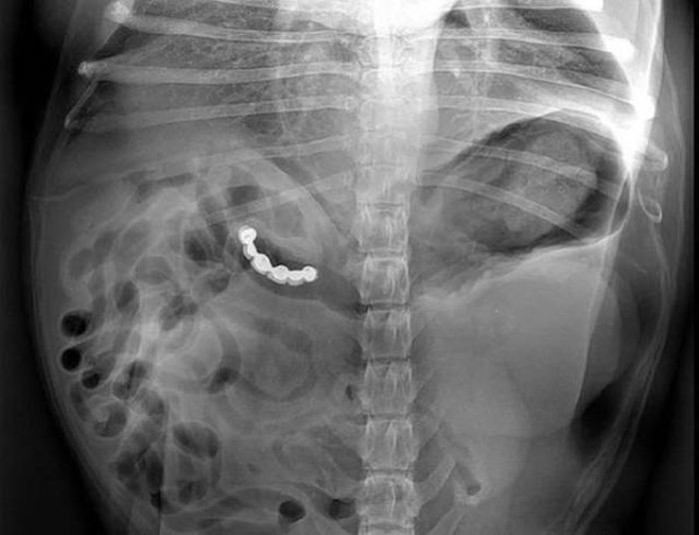

Предметы, которые не очень хочется видеть внутри себя

Под рентгеновскими лучами порой видны не только внутренние органы и кости, но и инородные тела, попавшие в организм

Истории попадания этих предметов в организм могут быть самыми невероятными и запутанными, но больше всего медиков интересует процесс их извлечения, впрочем, в этом заинтересованы и сами пациенты, допустившие нечто подобное со своим телом.